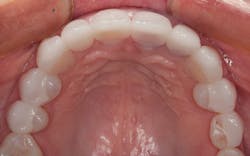

The final result can be seen from the occlusal view in Figure 9 and the retracted facial view in Figure 10. The patient’s new smile can be seen in Figure 11. Utilizing IPS e.max crowns and veneers, we were able to enhance the patient’s smile by creating a lighter color and a wider, more attractive look.

Figure 10: Retracted facial view of the final restoration